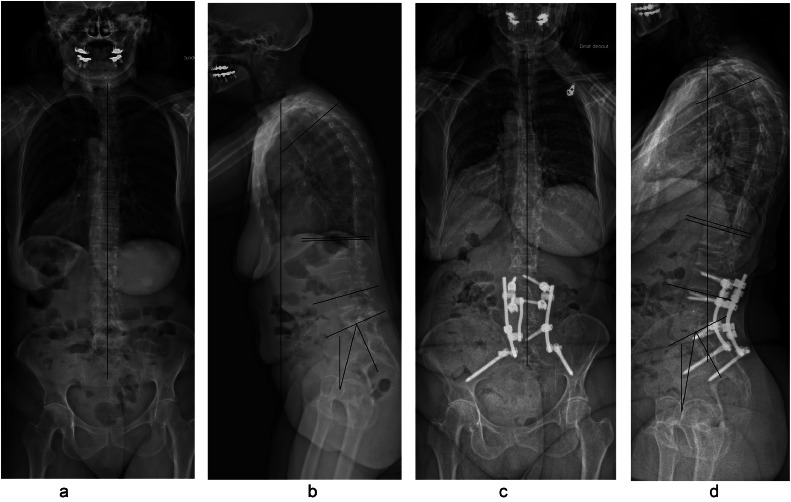

Fig. 3.

Fifty-five y old patient with postoperative flatback. Preoperative full spine anteroposterior and lateral X-ray showing sagittal and coronal malalignment in a Roussouly type 4 patient (high pelvic incidence), and the apex of lumbar lordosis is at the level L1L2 (A and B), C7-CSVL=8 cm, coronal Cobb=20°, PI=88°, PT=46°, SVA=9 cm, LL=−60°, TK=41° Postoperative full spine anteroposterior and lateral X-ray after L5 PSO demonstrating improvement of lumbar lordosis with its apex at the L3L4 disc level, C7-CSVL=5 cm, coronal Cobb=1°, PI=86°, PT=32°, SVA=2 cm, LL=−70°, TK=38° It should be noted that the domino is placed at the opposite side of coronal imbalance in order to achieve simultaneous correction of both planes.